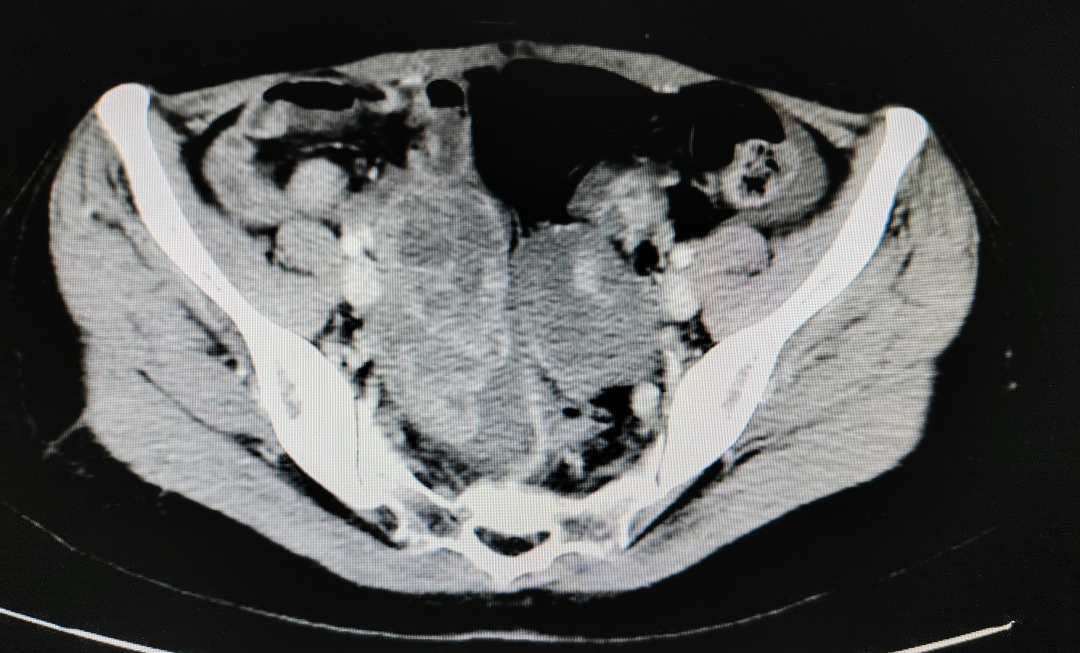

姚女士的CT报告显示:

肿瘤广泛转移,肝脏周围病变连成片,累及肝门,包绕门静脉,这个位置因“风险高”常被称为“手术禁区”,无论是对患者还是对医生,都要承担巨大的风险。

而放疗科、介入科专家则表示,放疗和介入治疗不适合姚女士当前病情。 姚女士的肝脏病灶影像▽